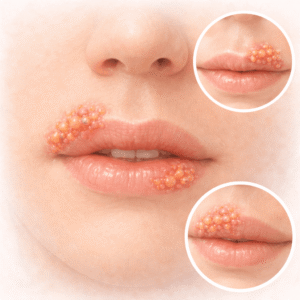

How Long Do Herpes Outbreaks Last And How To Deal With It?

Having a herpes outbreak is like having your own war, one that’s…

How to Get Rid of Cold Sores Quickly with Valaciclovir

Cold sores can strike you at the most inconvenient time, and you’re…